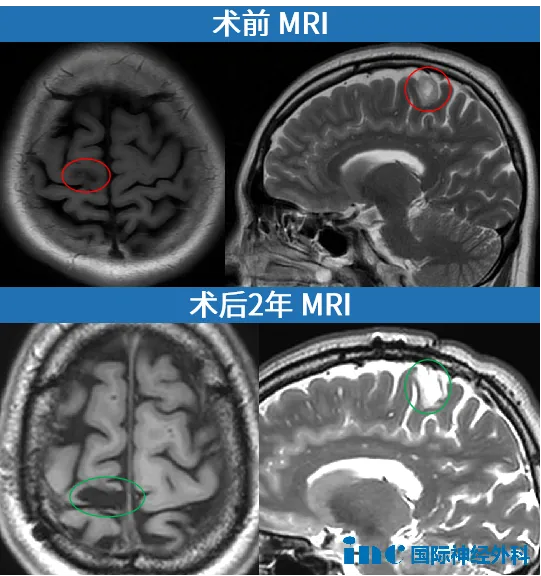

从咨询到手术,我只用了不到一个月。2022年12月4日,巴教授在苏州为我主刀,肿瘤被完全切除。

术后一年邮件随访评估中巴教授也表示:“低级别胶质瘤被完全切除,我们没有发现任何残余,附近的大脑结构和浅静脉是完整的。“

术后2年随访

“肿瘤得到全切,没有局部副作用,这确实是一个值得高兴的临床结果,她的状态看起来也非常好。此外,她的照片也展现出了极佳的精神面貌!我建议她继续每1.5年左右进行一次常规的核磁共振检查。目前,她无需接受任何特殊的额外治疗。”

——INC巴特朗菲教授